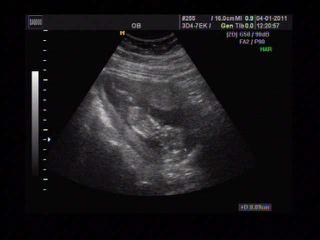

Kuratkol, krásný obrázek z ultrazvuku 😵 jak se cítíš?

Ahojky, tak jsme byli na kontrole - tentokrát i s manželem.